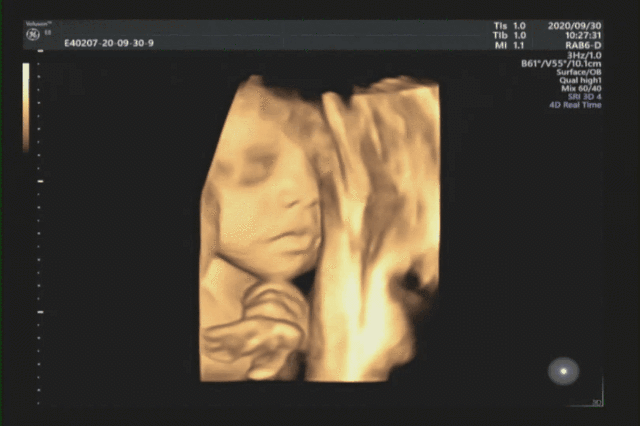

四维彩超是孕期排畸时十分常用的方式,检查宝宝的健康情况,排查出畸形的宝宝。

可以让孕妈和医生清楚真实的看到宝宝的发育情况,让孕妈第一时间见到自己宝宝的样子~

四维彩超的全称是四维彩色超声诊断仪,是彩色超声设备。

四维彩超能够表面成像,可以查看胎儿是否先天性体表畸形,如脑膜膨出,是否唇腭裂、脊柱裂等先天畸形,并为胎儿先天性心脏疾病提供准确的科学依据,及早发现及早地做出解决方案